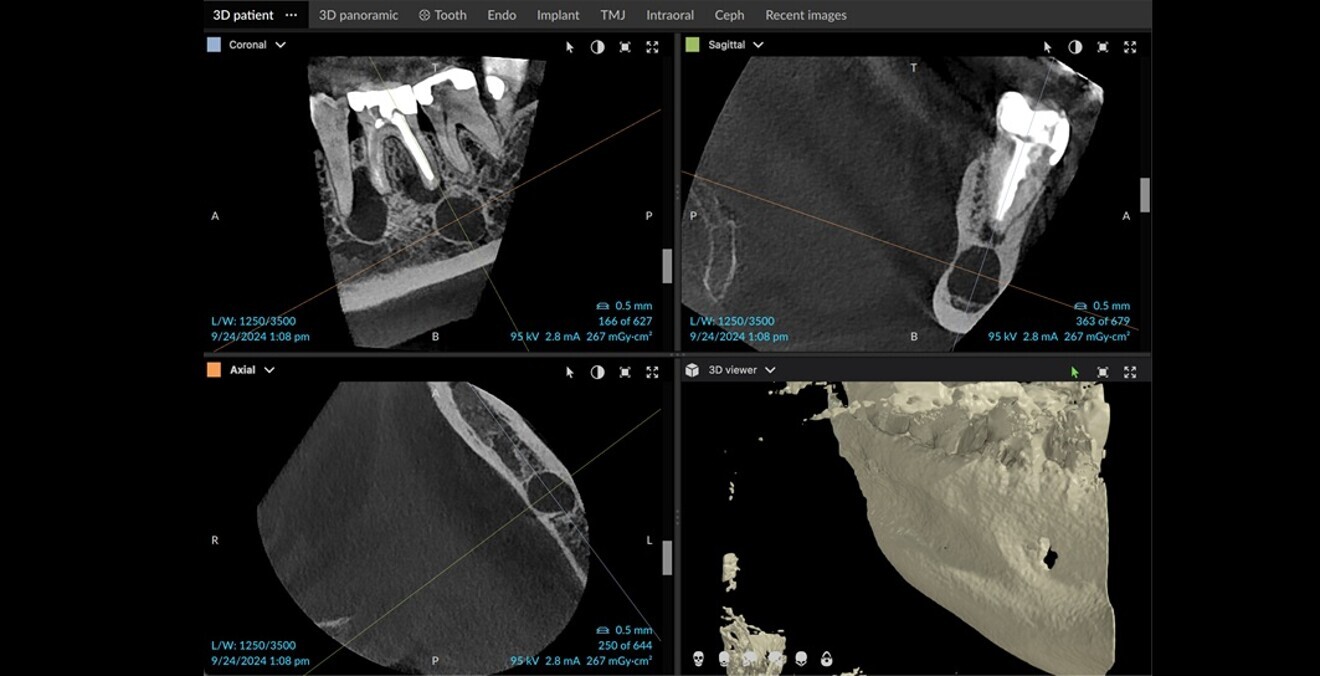

Figs. 11a–e: Axial and coronal views of the CBCT scan showing the quality of the bone in this typical bisphosphonate-associated bone necrosis case.

In this second case, the patient was referred by his general dentist for retreatment of his molar owing to pain on chewing (Fig. 10). On the medical file, treatment for melanoma was noted. Further questioning determined that he was taking bisphosphonate, among other medications. At this point, a CBCT scan was taken, and on it, we could see the quality of the bone clearly, including sequestra, typical of bisphosphonate-associated bone lesions (Figs. 11a–e). The reason for the occurrence in this area was the infection of the distal root due to a canal that had been missed during the root canal procedure. We consulted with the patient’s treating doctor, who recommended a long course of treatment with antibiotics for the interim and management of the necrotic bone that was showing under the tooth from the lingual side (Figs. 12a–d).